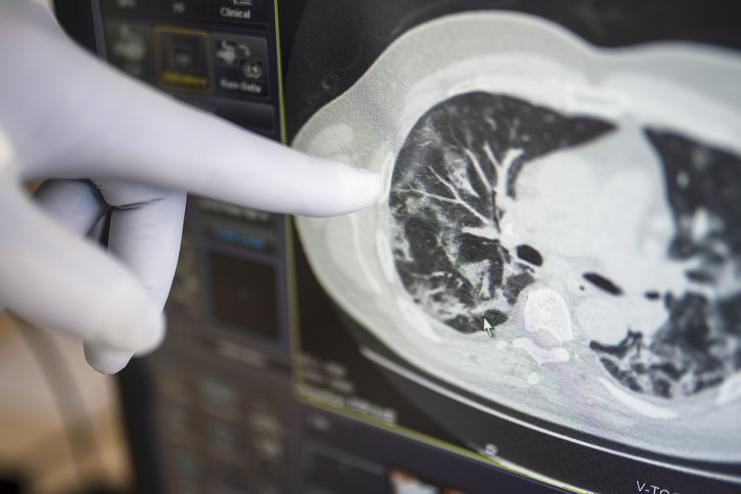

Матовое стекло - это усиление легочного рисунка, которое вызвано интерстициальным воспалением стенки альвеолы. Если проще, наши легкие состоят из маленьких микроскопических «пузырьков» - альвеол. Альвеолы же имеют стенку, по ту сторону которой, капилляры. По капиллярам «бежит» венозная кровь, которая насыщается кислородом и отдает углекислый газ. Так вот «матовое стекло» - это воспаление той самой альвеолярной стенки, но это неспецифический признак. Если воспаление альвеолярной стенки – будет матовое стекло . Но вот что вызвало воспаление – это другой вопрос, и причин может быть много. Да, врач соберет анамнез, узнает, что пациент, например, контактировал с человеком, у которого подтвержден ковид. И связав все воедино с 90% уверенностью будет утверждать, что вероятней всего причина «матового стекла», недомогания пациента и прочих симптомов – коронавирус. На рентгенографии матовое стекло не разглядеть, максимум рентгенолог опишет это, как «усиление легочного» рисунка. Тут бы на помощь пришла УЗИ-диагностика, но у нас в стране это непопулярный, а чаще неизвестный метод обследования легких. В Европе УЗИ легких - это стандартное обследование , а вот КТ как раз-то делают редко, потому что дорого и, главное, не влияет на тактику лечения.

Но вернемся к КТ. Вы все-таки решили сделать томографию легких и у вас описали «матовое стекло», некоторые даже считают процент поражения легких, хотя нигде в мире нет четкого алгоритма или схемы подсчета площади поражения легких – это уже наше «местечковое ноу-хау». Что делать?